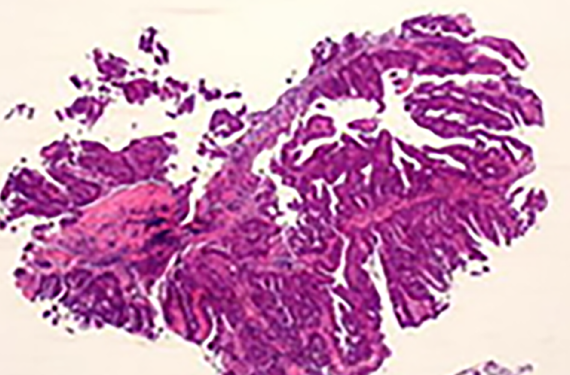

病理診断には細胞診、組織診断、術中迅速診断、病理解剖があり、組織診断はまず、病変の一部を採取し、顕微鏡を通して病気の診断を決める"生検"が行われ、その後、外科的な手術により切除された病変全体の詳細な診断により、治療方針が決定されます。臨床医との緊密な連携のもとで、的確な病理診断は患者さんにより優れた医療を提供することが可能になります。